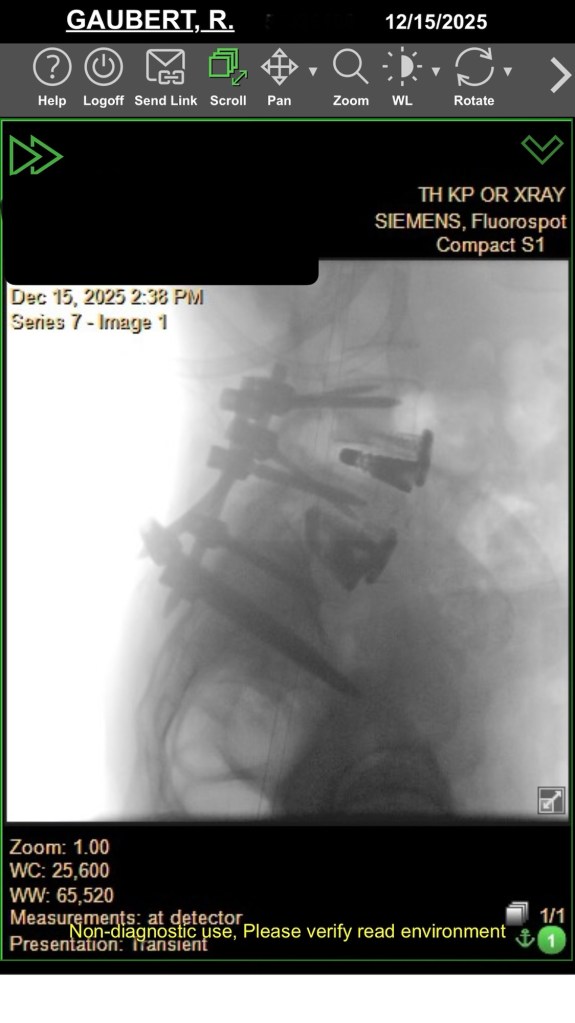

At my 3-month post-op appointment, my surgeon lifted all my restrictions and said I can return to all activity, “just listen to [my] body.” She measured my X-rays (above) and said my lumbar curve decreased 20 degrees, and the thoracic is the same. Also, I grew half an inch. I showed her the scoliosis program I found in New Hampshire, and she was all for it. I’ve booked a furnished apartment in New Hampshire 4/20-5/31 and scheduled the 12 sessions of treatment at the PT clinic there. I’m hopeful that will help with my back pain, and maybe even reduce my thoracic curve. And right before that, I’ll be attending Bionicon!